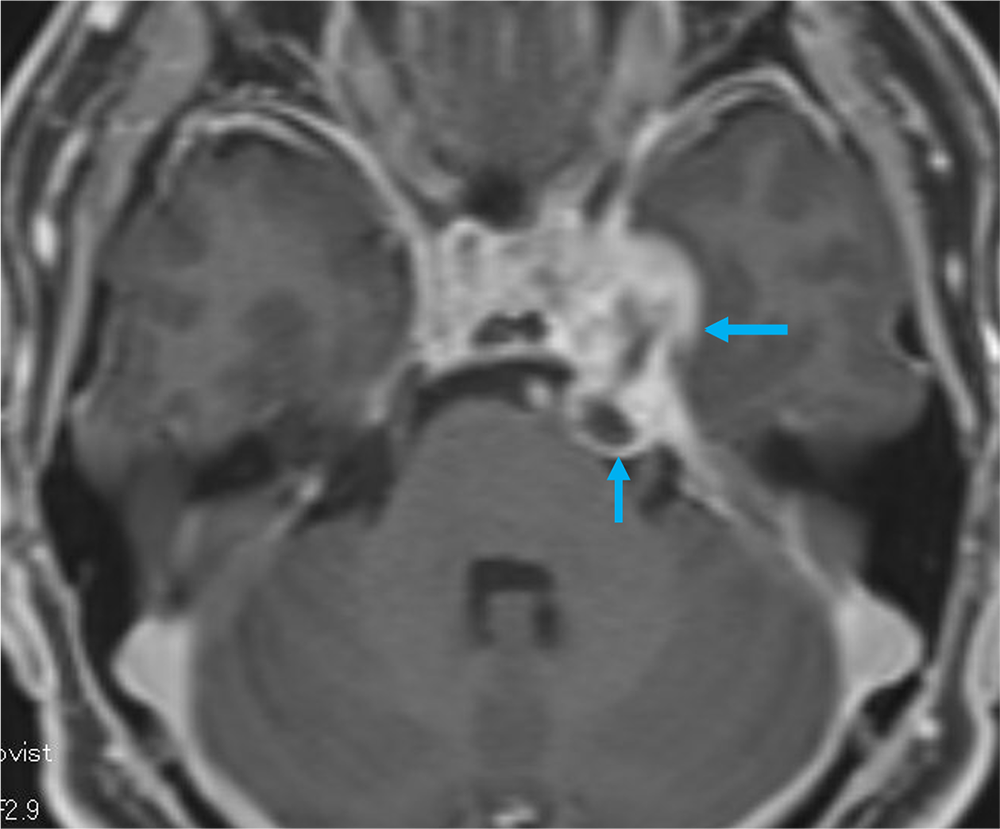

単純MRIのT2強調画像では左メッケル腔から背側に突出する腫瘍を認め、三叉神経鞘腫と髄膜腫が鑑別となる。Gd造影剤の脂肪抑制T1強調画像では腫瘍は全体に濃染し、冠状断では卵円孔を介した頭蓋外進展が見られ、三叉神経鞘腫の可能性が高い。内側では海綿静脈洞を圧排、背側では橋の軽度圧排も見られる。有症状であり、手術が施行され、三叉神経鞘腫と診断された。

三叉神経鞘腫を確実に診断するためには、神経走行に沿った進展を確認することである。Gd造影剤を用いた3Dの脂肪抑制T1強調画像を撮影することで、thin sliceの造影CTと同様に後から再構成したMPRを作成するにより、腫瘍の進展方向を確実に診断することが可能であり、本症例には必須のシーケンスと思われた。